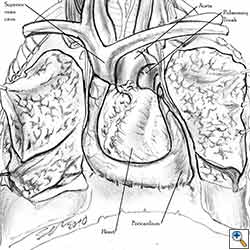

Pericardial reconstruction after anterior mediastinal tumor resection

Some pericardial defects resulting after partial pericardiectomy for invasive anterior mediastinal masses need pericardial reconstruction (Figures 4a-c). This is not the case for small pericardial defects, but large and lateral defects require reconstruction, especially if a lung resection has been performed. In the case of pericardiectomy with pneumonectomy, the postpneumonectomy space plays an important role in the pathogenesis of cardiac herniation. En bloc resection of a mediastinal tumor, the pericardium and the lung increases the risk of herniation in a similar fashion. In the absence of a lung resection, lung atelectasis can also increase this risk. Following complex resections requiring vascular resection followed by reconstruction, the reconstruction can stabilise the vascular prosthesis and prevent it from kinking (Figure 4c). Another potential advantage of pericardial reconstruction is that in the event of a re-do sternotomy, the risk of cardiac laceration is reduced because it prevents sternal-cardiac adhesions from forming [5]

Video 1 depicts a pericardial reconstruction with Marlex after a right completion pneumonectomy with pericardiectomy for lung adenocarcinoma (see also Figure 1). The technique of pericardial reconstruction after the resection of invasive mediastinal tumours is illustrated in Figures 8a-c). Video 2 depicts a pericardial reconstruction with Mersilene mesh after the resection of a malignant thymoma invading the anterior pericardium (see also Figure 4b). The technique of right pericardial reconstruction after extrapleural pneumonectomy is illustrated in Figures 9a and 9b). Video 3 depicts a pericardial reconstruction using Gore-Tex Dual Mesh after a left extrapleural pneumonectomy (see also Figure 3). Care must be taken to prevent constriction (Figure 10).